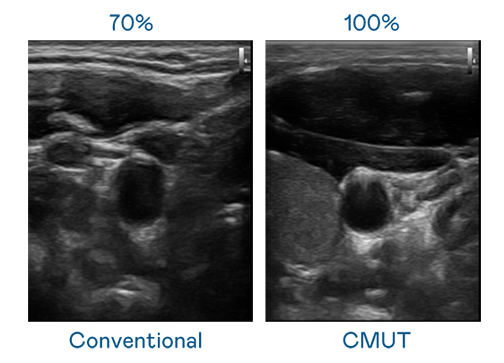

CMUT 技术是一种用电容式微机电元件来产生超音波讯号的技术。与传统 PZT 压电式技术相比,CMUT 频宽增加 30%,更宽频的超音波讯号让影像解析度大幅提升,是实现高影像品质医疗超音波扫描、促进精准医疗发展的关键技术。

大频宽带来超清晰影像

超音波影像的解析度高低,首先取决于探头能发出的讯号频宽。爱游戏体育 CMUT 可提供高清晰的超音波讯号,提供高频宽、高灵敏度、影像纹理细节更高的超音波影像,协助医护人员缩短影像判读时间及利用精准的医疗影像进行诊断。